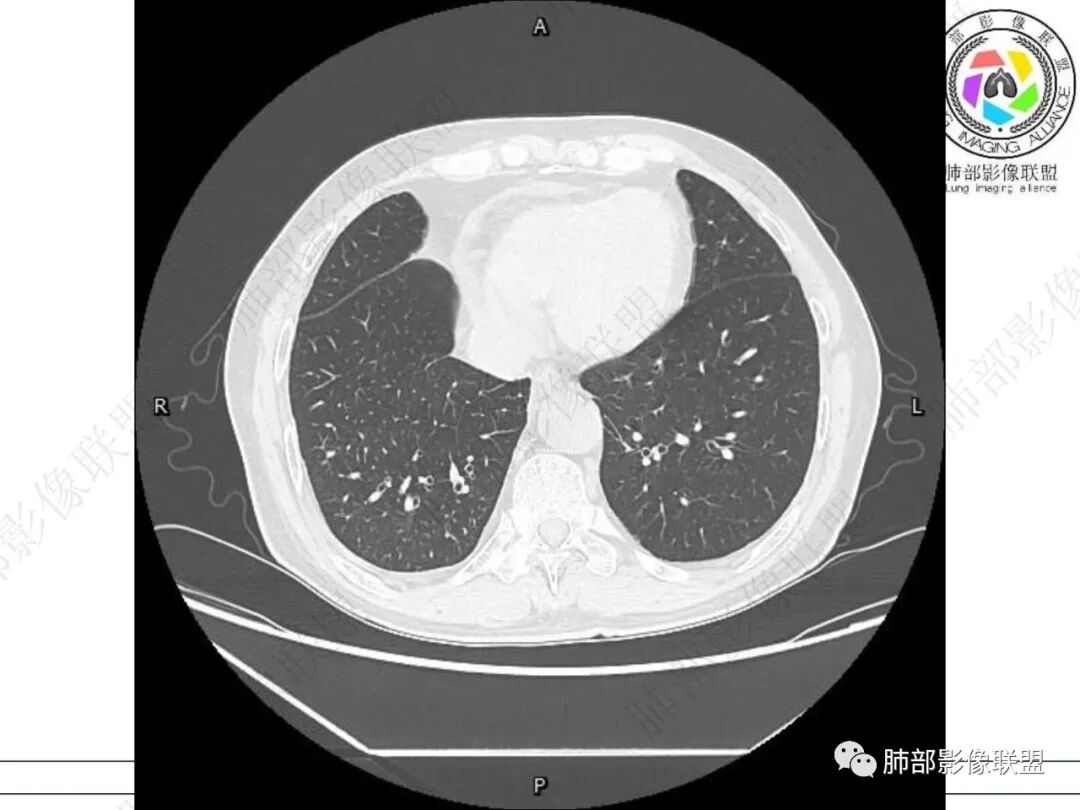

右肺下叶背段可见斑片状、条片状高密度影,支气管扩张,周围伴有磨玻璃影,边界欠清,纵隔窗:可见脊柱偏右侧可见斑片状影,与食管交界面欠清,食管形态不规则,考虑食管支气管瘘?食管异物穿孔?支气管异物?建议食管镜及支气管镜检查。

右肺下叶背段条片状实变影,内可见支气管走行,支气管有狭窄有扩张,周围可见磨玻璃影,隆突下团片影,内密度不均可见气体影,与周围结构界限不清。食管下段壁增厚,管腔狭窄,右肺下叶慢性炎、肺不张,考虑食道肿瘤所致气管食管瘘。

右肺下叶沿肺叶肺段分布斑片、条片状影,以下叶背段为显,边缘模糊,内可见支气管走行,局部支气管管壁增厚,右侧胸腔少量积液。纵隔隆突下可见不均匀软组织密度影,与周围结构分界不清,内见气体密度影,与食管及相邻右肺支气管之间未显示通道。邻近食管下段壁明显不规则增厚,增强后食管管壁明显不均匀强化,可见线样强化的连续完整粘膜影。